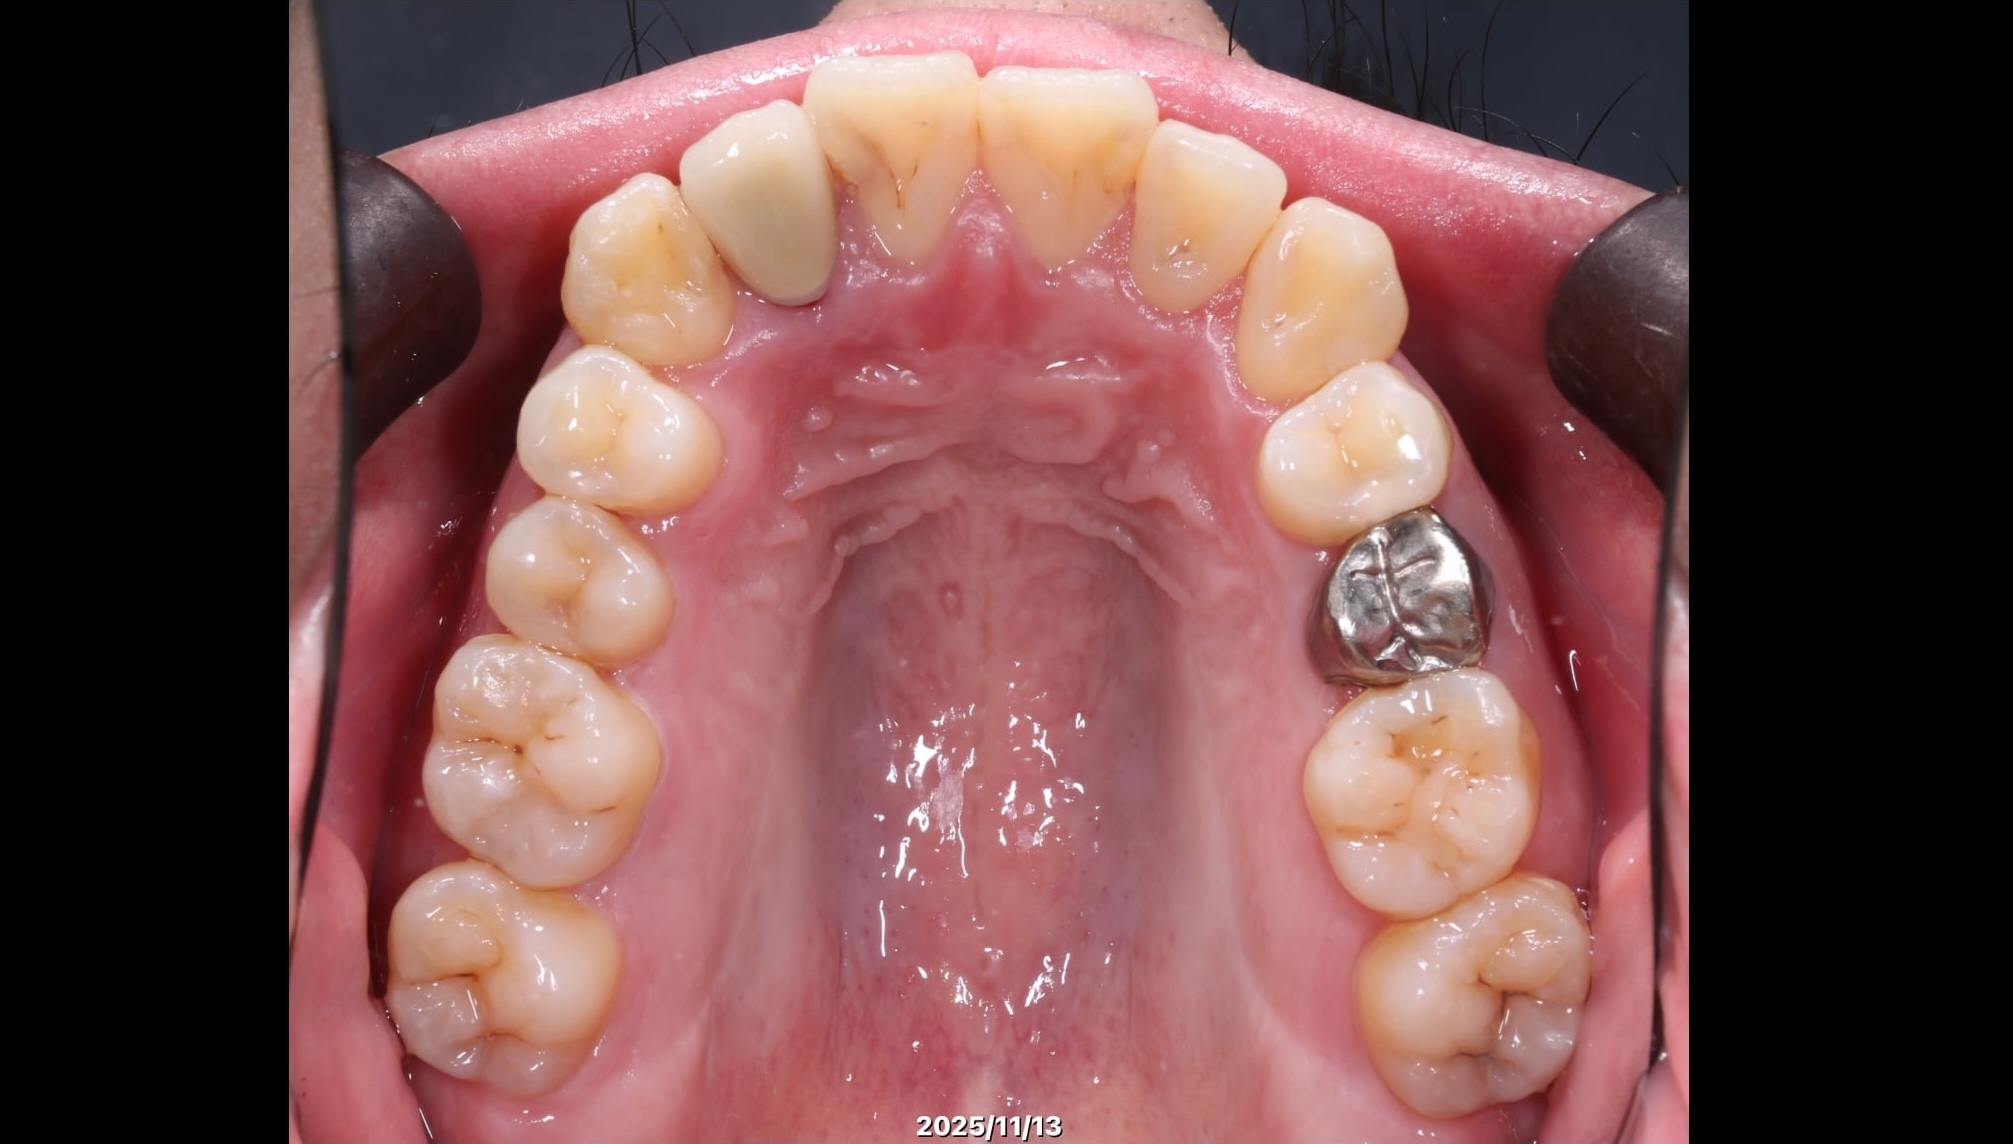

症例2:叢生を矯正治療で改善した症例

術前の状態

術後の状態

治療概要

| 患者さんの状態 | 叢生 |

|---|---|

| 治療内容 | MEAWを用いた矯正治療(非抜歯) |

| 治療期間 | 約2年 |

| 治療費用 | 1,320,000円(税込) ※矯正治療費のみです。 |

| 治療のリスク | 歯肉退縮、自由診療、後戻り、口腔内清掃が難しい |